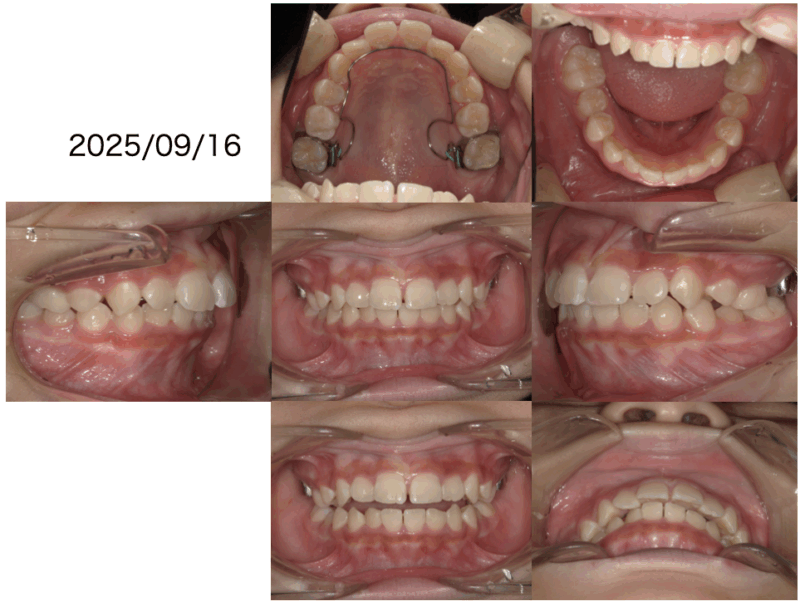

凸凹改善2025年10月21日Written by 土持歯科クリニック主訴は凸凹でした。お口を開けてる状態を見ると上下のバランスも悪いです。原因は口呼吸です。まずは鼻呼吸に改善しましょう。鼻呼吸に変わったことで、少し良くなりました。下の前歯の凸凹と上顎の糸切り歯の隙間が足りません。次のトレーニングを始めました。トレーニングが上手くいってます。裏側から見えない装置で糸切り歯の隙間改善に取り掛かりました。一見綺麗に思えますが。上顎の歯が全部大人の歯に変わるまではトレーンーニングを親子で頑張ってください。